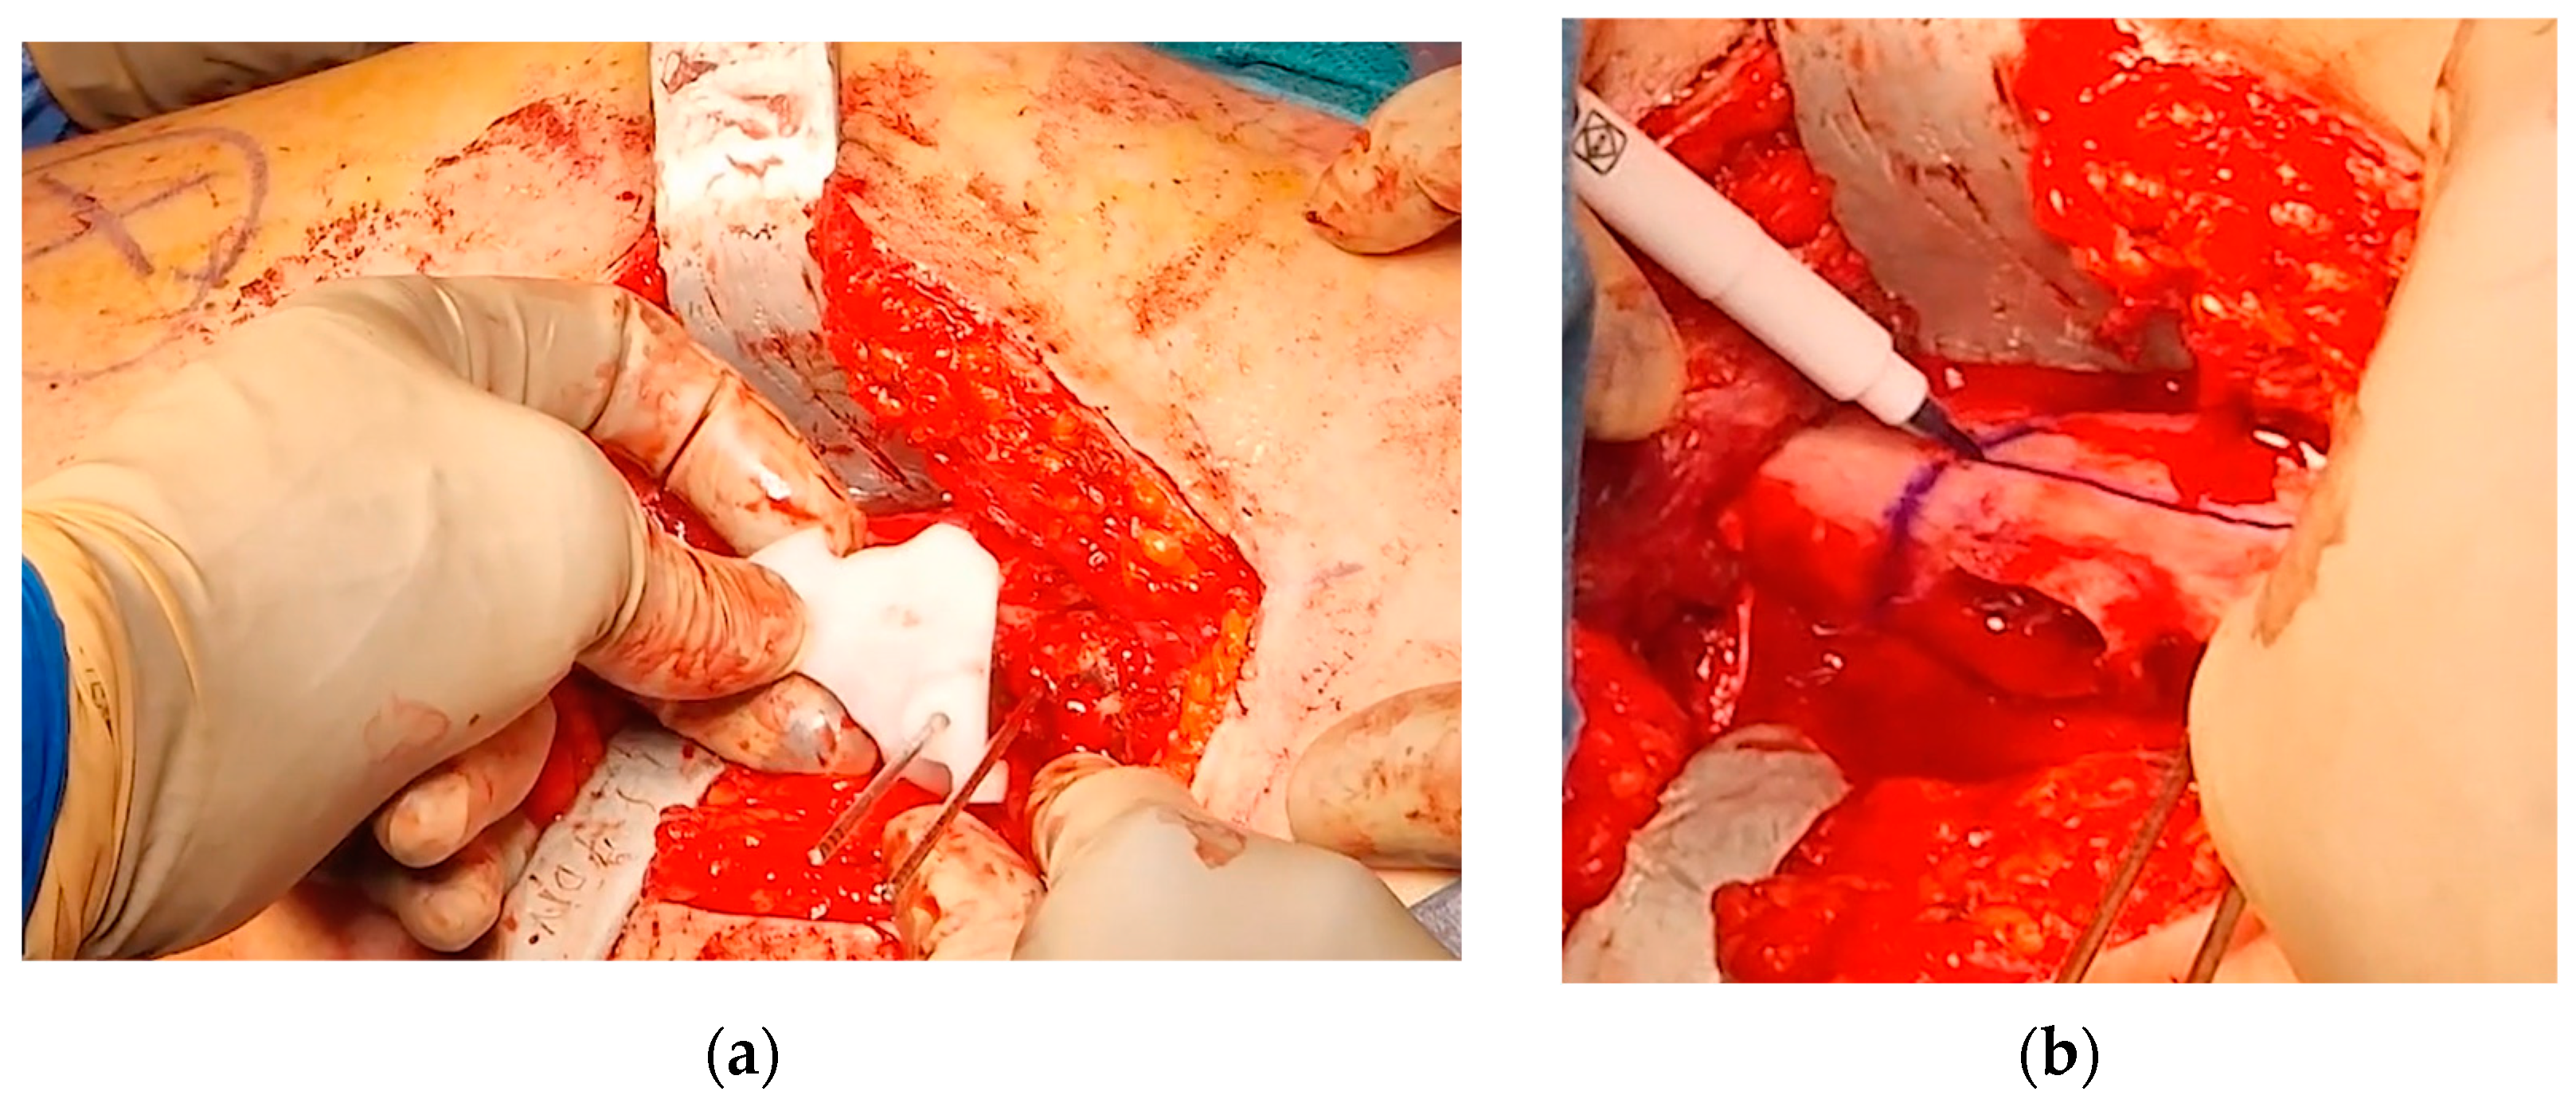

2.1. Virtual Surgical Planning and Design of 3D-Printed Cutting Guide

2.2. Surgical Procedure